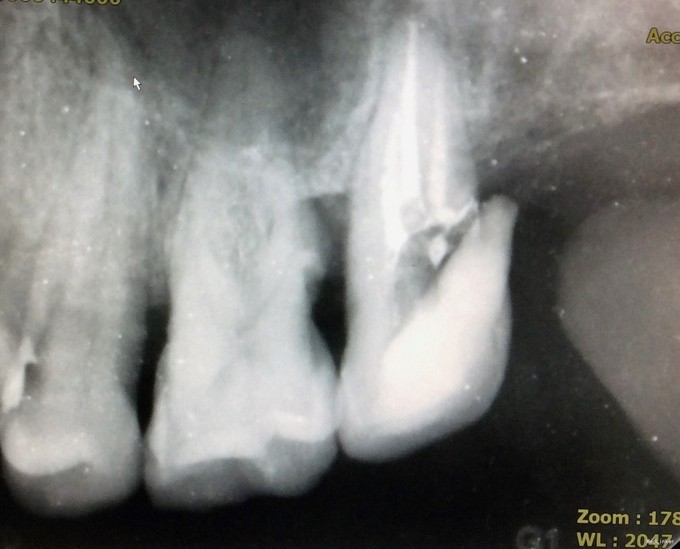

检查:27牙远中邻he面见大面积龋坏组织,质软,探及穿髓孔,探(-),叩(+-),根尖区扪(+-);松动I度;颊侧牙槽粘膜及牙龈未见明显窦道。28牙于我科就诊时已拔除。 全景片示27牙远中低密度影,累及髓腔;无清晰根管影像;牙槽嵴高度正常;牙周膜间隙正常;根尖周组织未见低密度影。

1、从全景片中可见,该牙龋坏已与髓腔相通,髓腔较为明显。但开髓时发现,髓腔内几乎均钙化,髓腔空间及其狭小。且该牙解剖牙冠长,且为上颌最后颗磨牙,若对牙体解剖没有足够地掌握,没有充足的经验,非常容易开髓开偏或找不到根管口,或有遗漏根管,因为近颊根根管口被钙化的牙体组织完全覆盖。此种情况下,若使用涡轮机企图去除牙体组织后寻找根管口非常困难,若在显微镜下使用超声则为最佳选择。 2、该牙虽然冠的上部牙体组织无去坏,但仍然去除掉了。虽然对牙齿的创伤较大,但若不去除这些无机釉,一来可能龋坏无法去除干净,二来抗力形不足,容易折断。 3、该牙髓腔内牙髓完全坏死,但各个根管内均有较好牙髓活力。说明牙髓的坏死是一个渐进的过程,即便是髓腔及根管开始钙化,牙髓也可有活力。